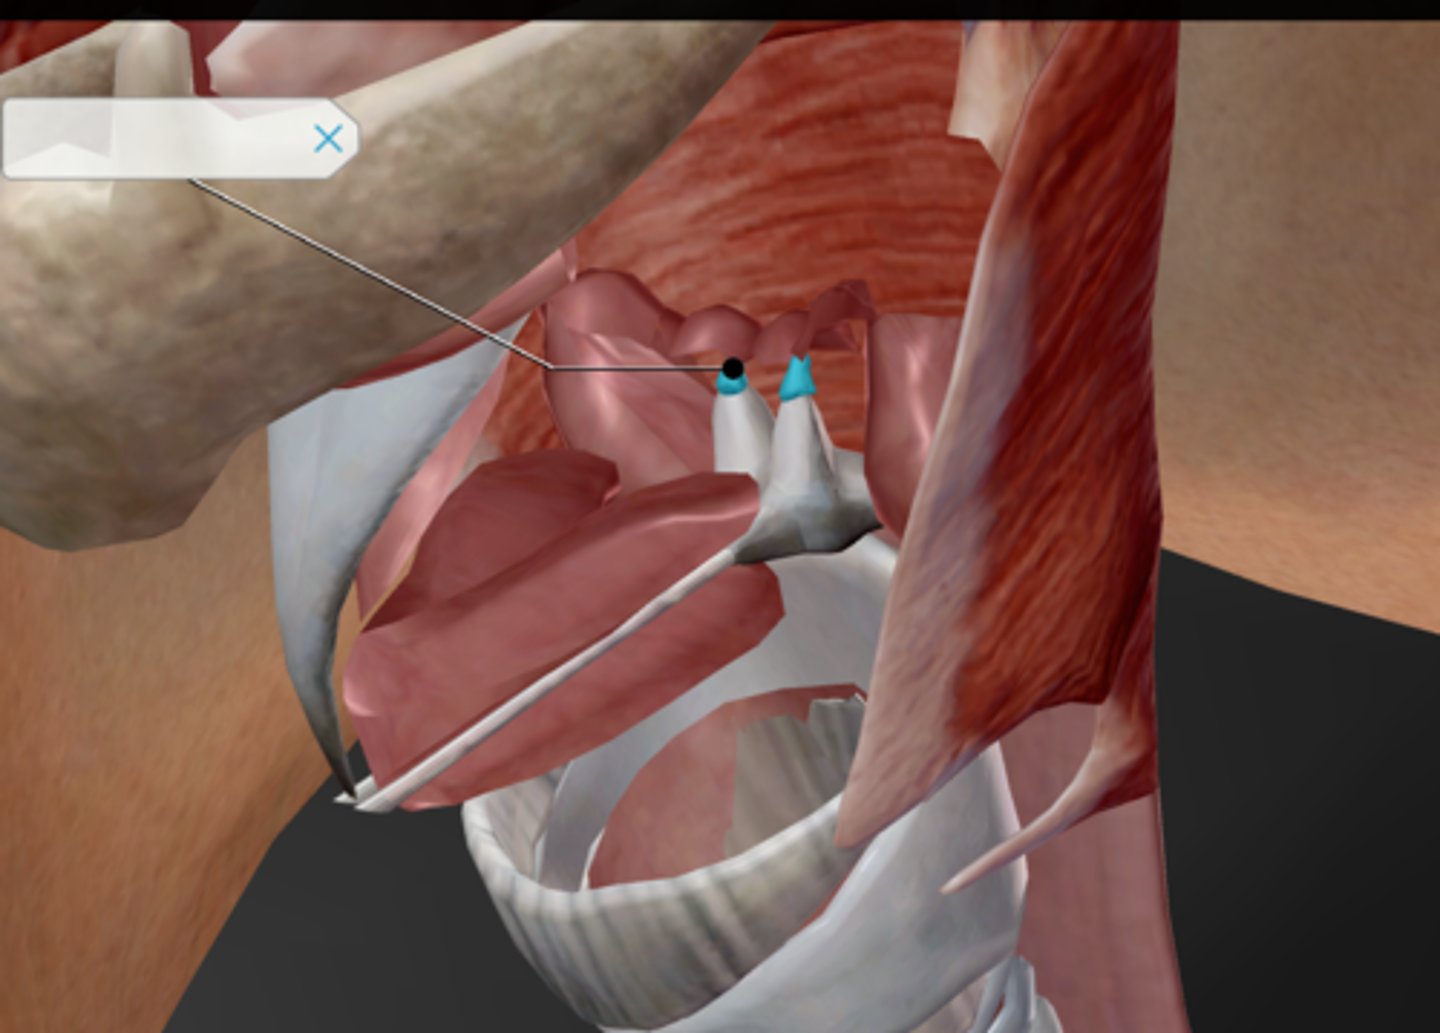

Larynx

Epiglottis

Thyroid cartilage

Cricoid cartilage

Arytenoid cartilage

Corniculate cartilage

Vocal ligament

Vocal folds

Vestibular folds